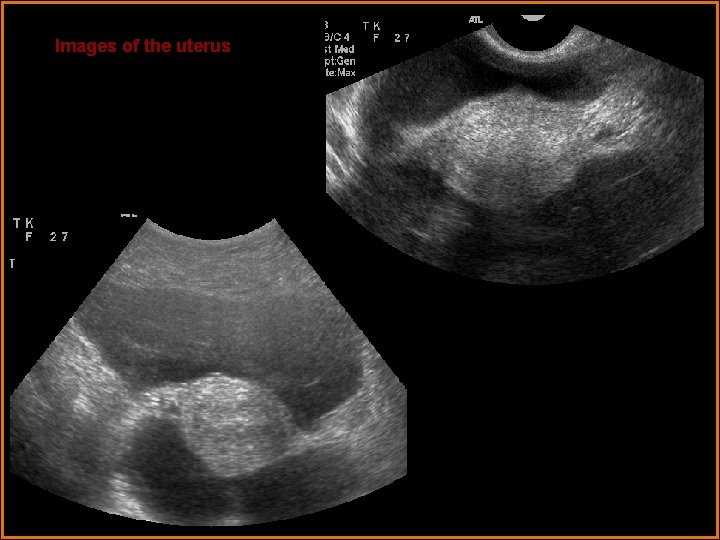

Images of the uterus

Findings and Differentials Ultrasound Findings: The ovaries are large with multiple enlarged follicles. The ovaries measure 10 to 15 cm each. Ovarian doppler flow was normal bilaterally. The uterus is normal is size with a normal appearing endometrium. Moderate ascites is present within the pelvis and abdomen. Differentials: • Ovarian hyperstimulation syndrome with pregnancy • Ruptured ectopic pregnancy • Complicated abscess with pregnancy